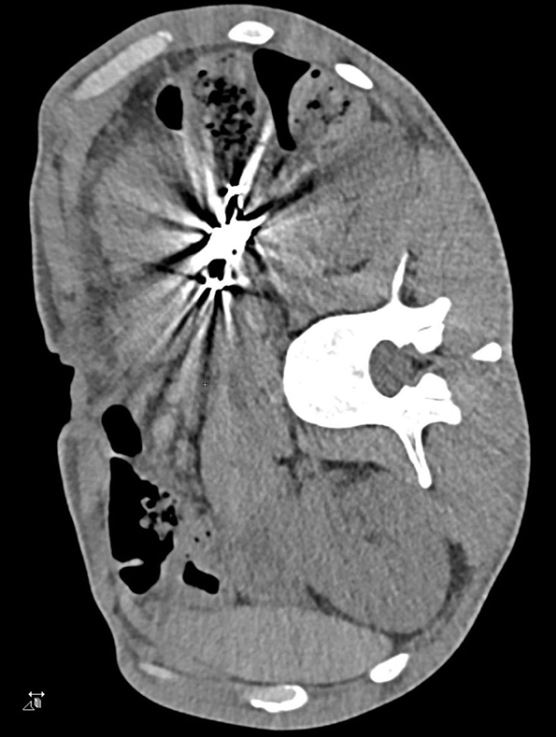

Seit zwei Wochen musste sich ein 42-jähriger Mann regelmäßig erbrechen; zudem hatte er über die letzten drei Monate 10 kg Gewicht verloren. Er wurde schließlich in einer internistischen Klinik vorstellig. Der Mann litt an einer schweren chronischen Schizophrenie, nahm aber keine Medikamente ein.

CT und 3D-CT-Rekonstruktion einer Raumforderung im Magen.

© CMAJ. 2024;196:E906-7